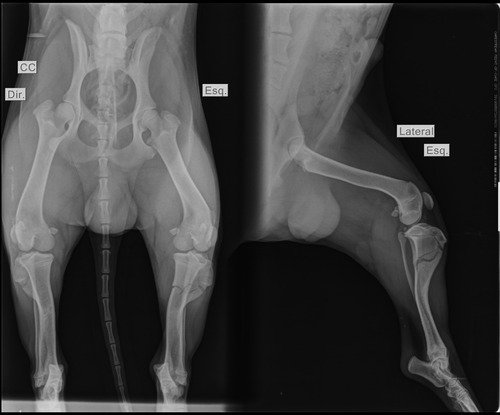

Ao levarmos ele para o veterinário no mesmo dia, descobrimos que além da fome, ele estava com anemia e o PIOR, havia sido atropelado e sua pata traseira estava QUEBRADA, o que justificava o medo que ele teve ao ser resgatado.

Ele estava com MUITA DOR, e por isso precisou passar por uma cirurgia ortopédica de emergência, e mesmo não podendo custear os gastos no momento, passamos o valor no cartão e dividimos do máximo de vezes que dava, para depois nos preocuparmos com isso. POIS o mais importante era aliviar o sofrimento dele.